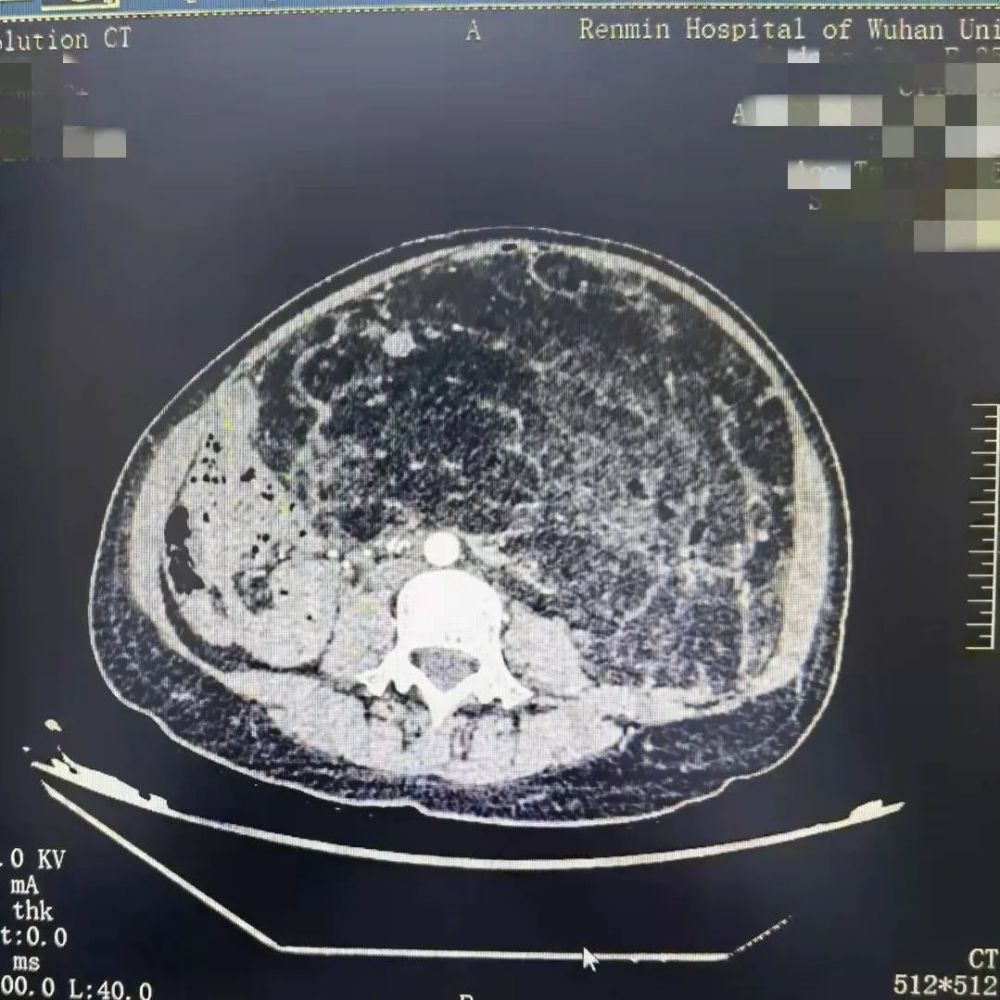

罕见巨大肾错构瘤

直径长达40厘米

重达14斤

足足占了腹腔近五分之四的空间

左肾更是被压迫移位到了右边

今年9月底,她发现自己的肚子明显变大了许多,左侧摸着还有硬硬的疙瘩。在当地医院CT检查发现,左侧的肾错构瘤已经疯长到了将近40厘米。由于肿瘤巨大,当地医院建议她到武汉治疗。

许女士慕名找到武汉大学人民医院泌尿外Ⅰ科吕胜启教授。进一步检查发现,这个罕见的巨大肾错构瘤,占据了腹腔近五分之四的空间,左肾更是被压迫移位到了右边,肾脏周围的胃、十二指肠、肝脏、胰腺、脾脏、子宫等重要脏器也跟着“遭殃”。